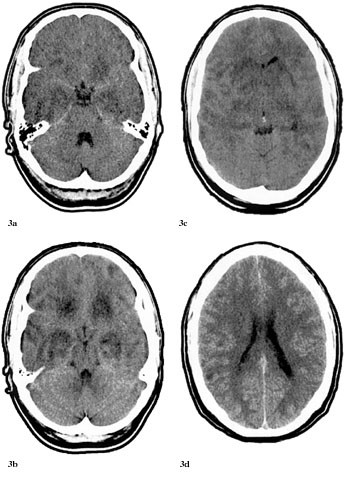

Pasient 2. En tidligere frisk 22 år gammel mann fikk i andre delen av mai 2000 halsbetennelse og tok penicillin. 31.5. utviklet han utydelig språk og kvalme. Dagen etter fikk han hodepine, han var trett og fikk hukommelsesproblemer. Ved innleggelse i lokalsykehuset var han ikke orientert, hadde amnesi for en uke tilbake, ellers var det normale nevrologiske funn. I vennekretsen hadde det forekommet tilfeller av infeksiøs mononukleose like før, men pasienten hadde verken forstørrede lymfeknuter, forstørret milt eller lever. CT med og uten kontrast var initialt vurdert som upåfallende, til tross for lettgradig asymmetri av sideventriklene (fig 1a). Infeksjonsparametere var uten anmerkning. 2.6. ble han utskrevet i velbefinnende. I løpet av de neste to dager virket pasienten eiendommelig, med humørsvingninger. 4.6. fikk han et generalisert tonisk-klonisk anfall og ble på nytt innlagt i lokalsykehuset. Tilstanden var vurdert som utløst av abstinensanfall etter moderat alkoholinntak. 5.6. ble han febril (39,0 ˚C), trett og fikk økende hukommelsesproblemer. Spinalvæskefunnet viste 7 × 10⁶ celler/l, protein 0,45 g/l, glukose 4,1 mmol/l; CRP var 21 mg/l, ASAT 31 U/l, ALAT 51 U/l, øvrige serumverdier var normale.

Dessverre hadde vi ingen mulighet til å få utført MR og obduksjon. Likevel er en akutt demyeliniserende encefalomyelitt mindre sannsynlig på grunn av at sykdomsutviklingen ikke kom helt akutt, men var gradvis innsettende i løpet av ti dager. Dessuten hadde man ikke fokale eller multifokale motoriske eller sensible utfall (10, 13). CT-funn viste progredierende, symmetriske forandringer som gav hypodensitet først i basalganglier og senere generelt, men hele tiden mest i basale deler av storehjernen og i de limbiske strukturer (fig 1 – 3). Retrospektivt aner man allerede ved første CT-undersøkelse (fig 1b) små hypodense områder ut for 3. ventrikkel på hver side lavt i basalgangliene. Disse funnene tyder heller på en atypisk encefalitt enn på en akutt demyeliniserende encefalomyelitt og korresponderer med de kliniske funn av hukommelsesproblemer og personlighetsforandringer. Pasienten fikk terminalt sentral respirasjonsstans, noe som kan tyde på hjernestammeaffeksjon.